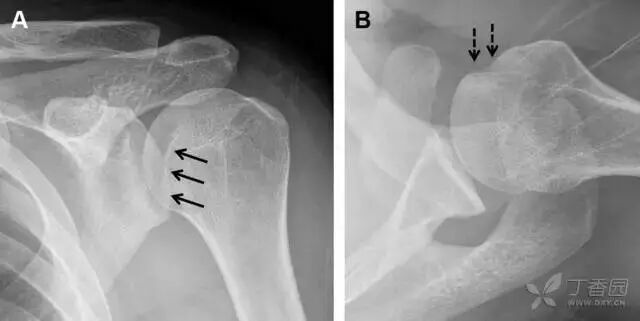

25肩胛骨骨折

肩胛骨几何形状复杂,受到邻近其它骨性结重叠阻挡,且肩胛骨骨折少见,因此容易漏诊。当存在解剖变异时,诊断更为困难。

图 3 肩胛骨骨折正侧位片:由于骨块的叠加,(A)前后位片示「V」形高密度影(*),肩胛颈下方可见骨皮质碎片(箭头);(B)侧位片示骨皮质中断,骨折段移位,但由于肱骨的重叠遮挡,决断往往比较困难

27肩峰骨折

肩峰骨折为高能量损伤,多由直接暴力导致,好发于中青年患者,多伴有肩关节其它结构损伤。有必要拍摄 Rockwood 位(前后位片,X 线束尾倾),特别有利于显示肩峰下部及肩峰下间隙。

图 5 肩峰骨折。内旋位前后位(A)片上,骨折线几乎被喙突完全遮挡, 但是在标准前后位(B)和腋位(C)片上可见骨折线